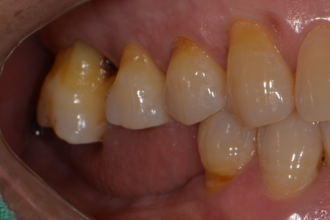

굿프렌즈 치과 임상 케이스

임플란트

심미보철치료